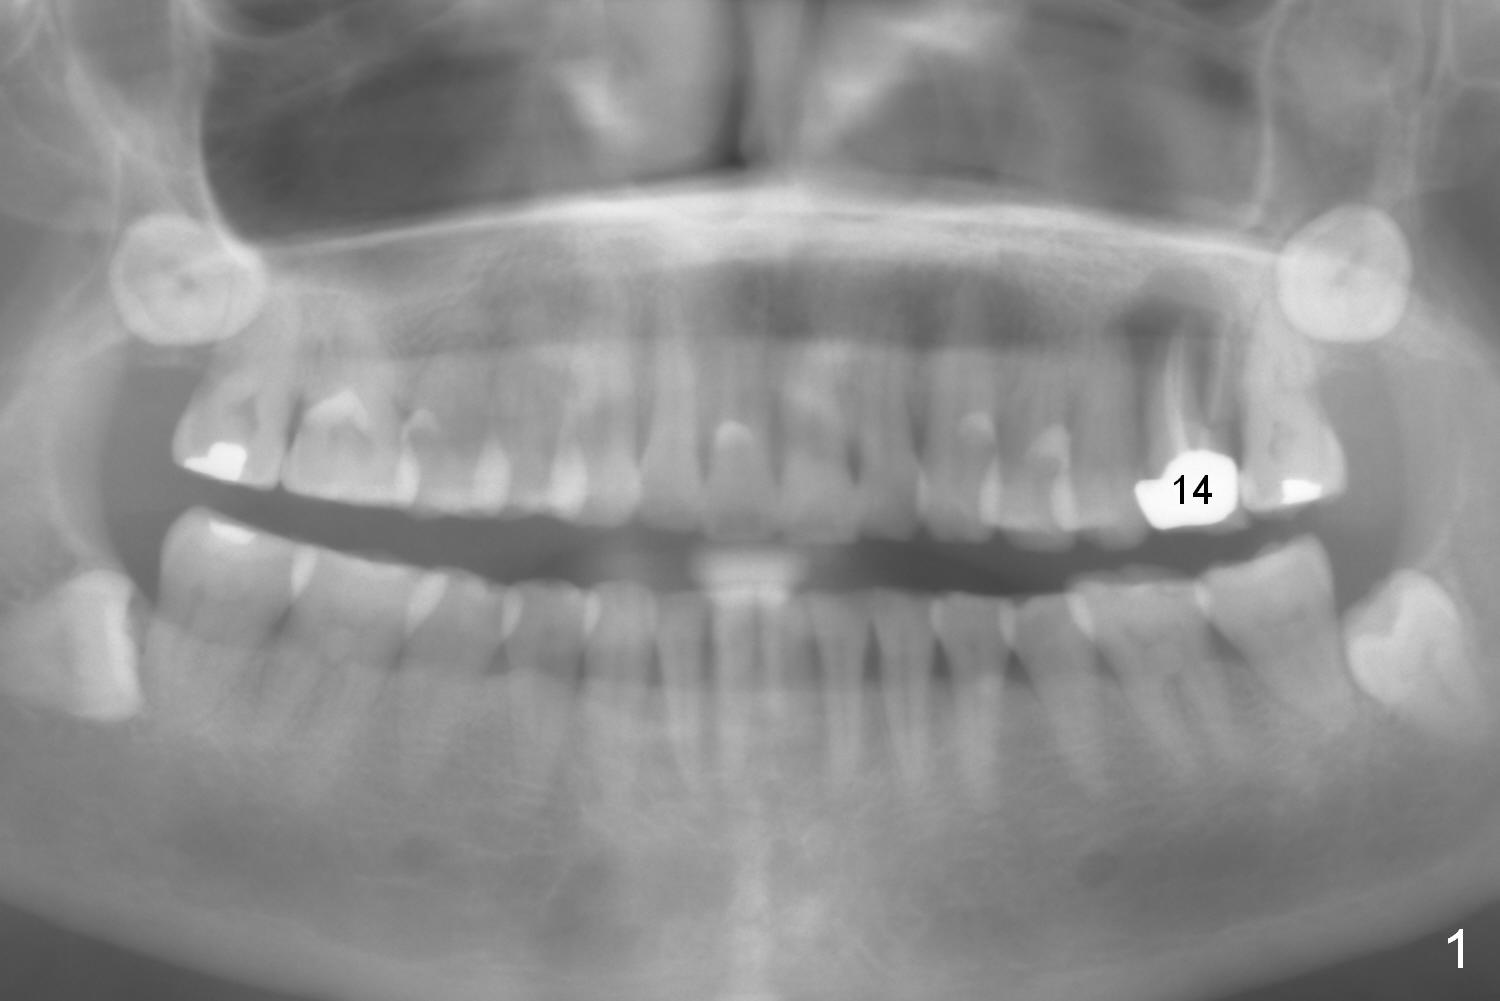

A 54-year-old woman has nocturnal pain at the tooth #2 (Fig.2), one year after extraction of the tooth #14 (Fig.1).  A mesiodistal crack line is found at root canal therapy (Fig.3 arrowheads).  The tooth appears to be nonsalvageable.  The socket is either single or 3.  Cut and soak 3 large pieces of gauze in Metronidazole.  When the tooth is extracted, we will decide whether the gauze needs to be cut further.  Depending upon the size of the septum, a relatively small (4.5x9 mm Fig.4) or large (6.5 mm) implant will be placed.  The largest pair abutment will be installed to close the socket.